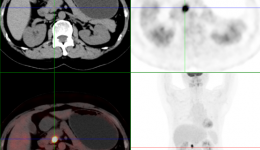

• 茂名一女士旅行前做了全身检查,万万没想到......

茂名一女士旅行前做了全身检查,万万没想到......

近日,茂名51岁的陈女士(化名)正准备外出旅行,却被医生告知检查发现了肿瘤,这是怎么回事呢?!原来,陈女士前几年接连患上了肾结石和肠胃炎,近年来十分重视身体健康问题,每年定期体检。由于陈女士准备在外出旅行前,做一个更全面的身体检查,...

• 粤西首台!影像检查重器数字化PET/CT落户茂医

粤西首台!影像检查重器数字化PET/CT落户茂医

粤西首台数字化PET/CT在茂名市人民医院核医学科完成装机调试,这台新型DMIPET/CT是数字化PET加64排128层诊断CT,一次扫描获得全身影像,是名副其实的全身体检项目,具有早期发现肿瘤病变或癌前病变的优势。这标志着茂名市人民医院的影像检查进入了...